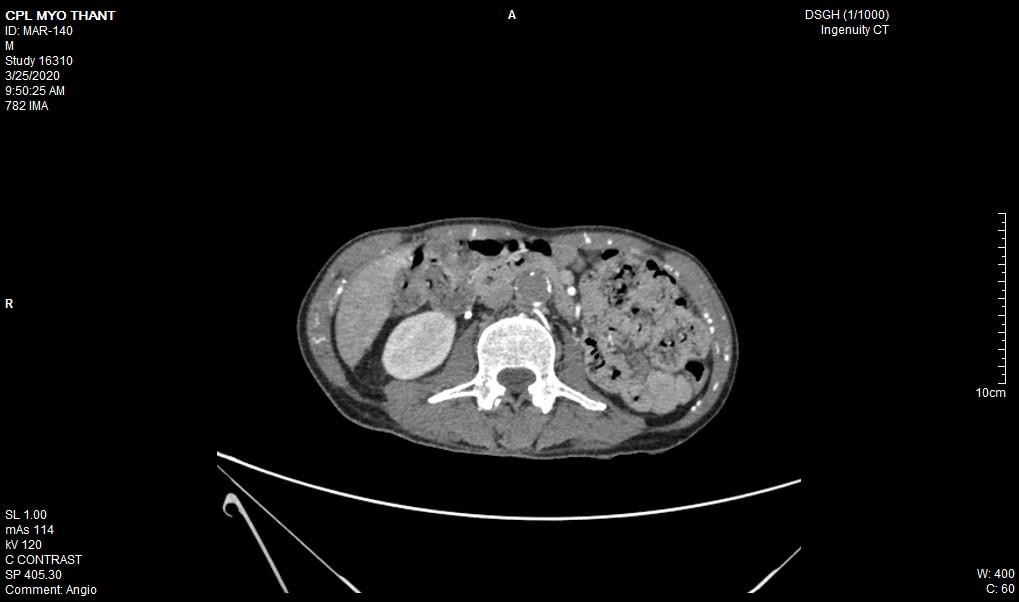

As his left femoral artery pulsation became weak and thus, CT Aortogram was done (4 weeks after symptom onset of right femoral artery occlusion). It revealed extensive thrombosis with complete obstruction of abdominal aorta starting below the level of celiac trunk- both renal arteries and both iliac arteries. The calcifications of the arterial wall at aortic arch, thoracic and abdominal aorta and both iliac vessels were seen too. (Figures 5-11) Thus, he had severe atherosclerosis due to hypertension and heavy smoking. Occlusion of both renal arteries explained his high blood pressure. The cholesterol and uric acid level were normal. He was treated with atorvastatin, aspirin, clopidogrel, antihypertensives, wound care, physiotherapy, intensive nursing care nutritional support and antibiotics.